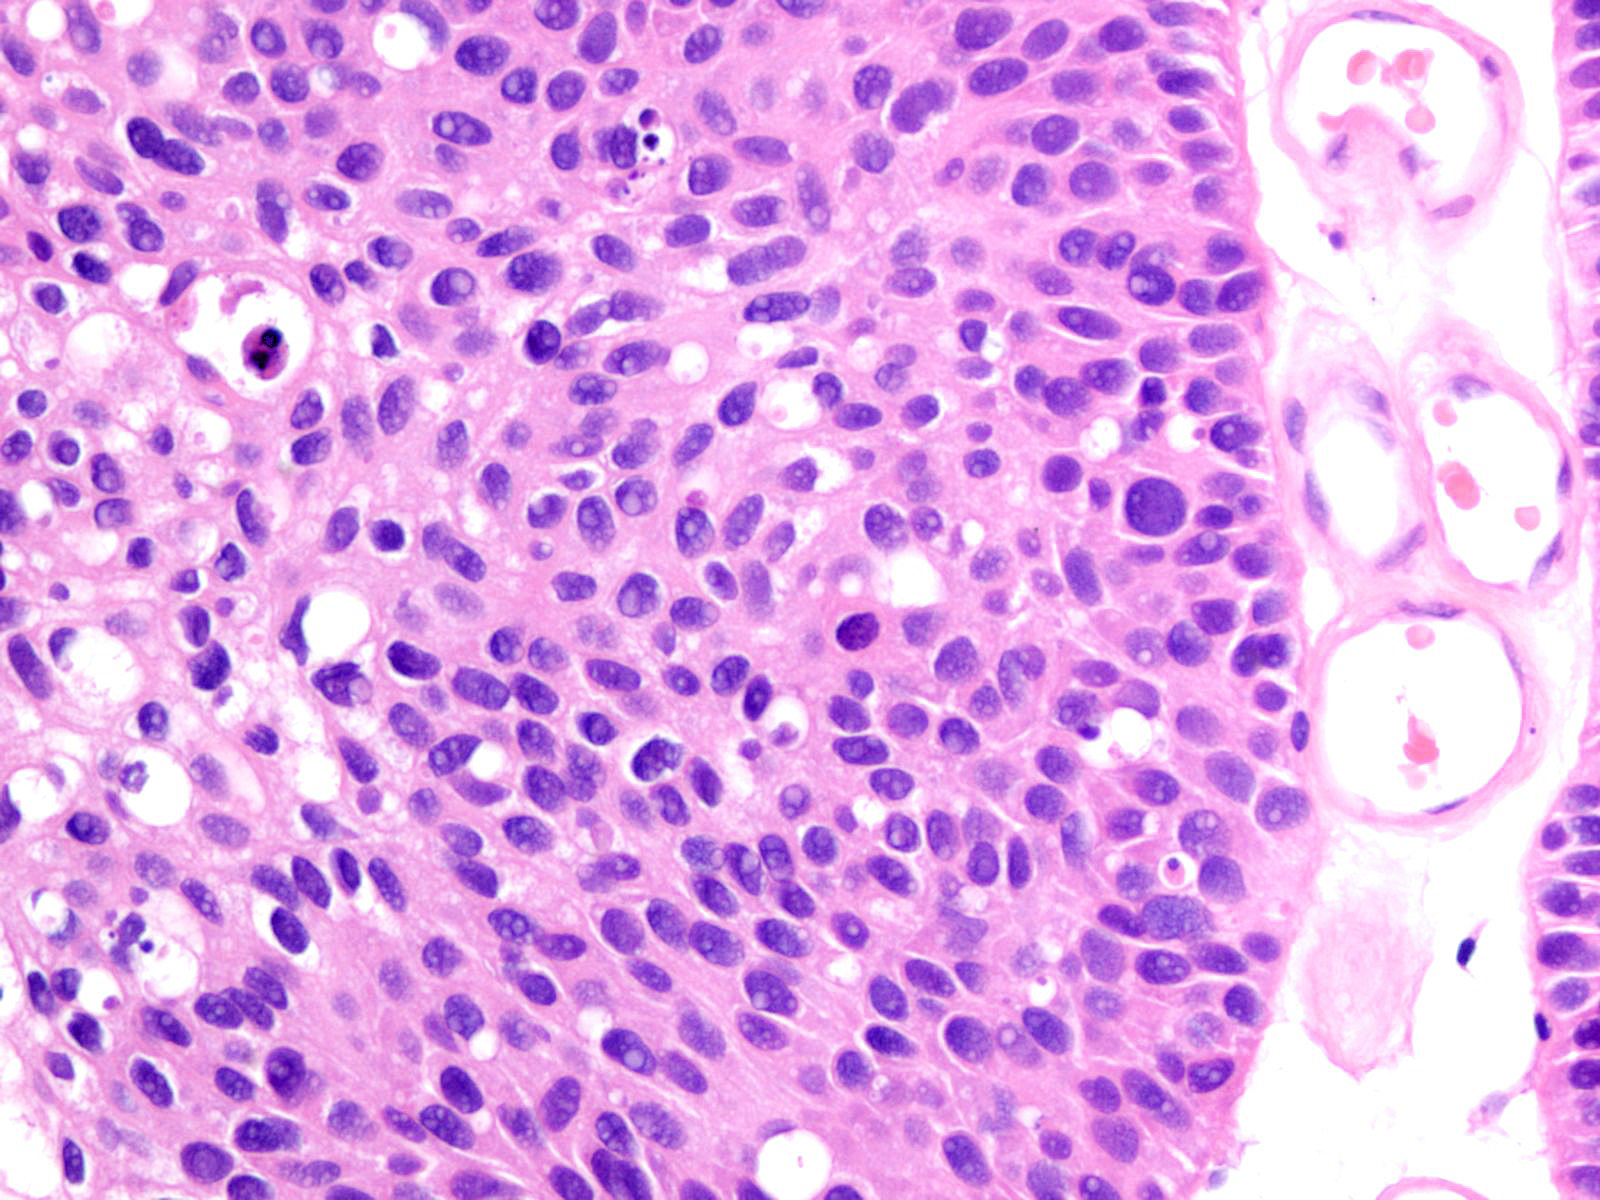

Bladder Papillary Lesions

Case ID: 212